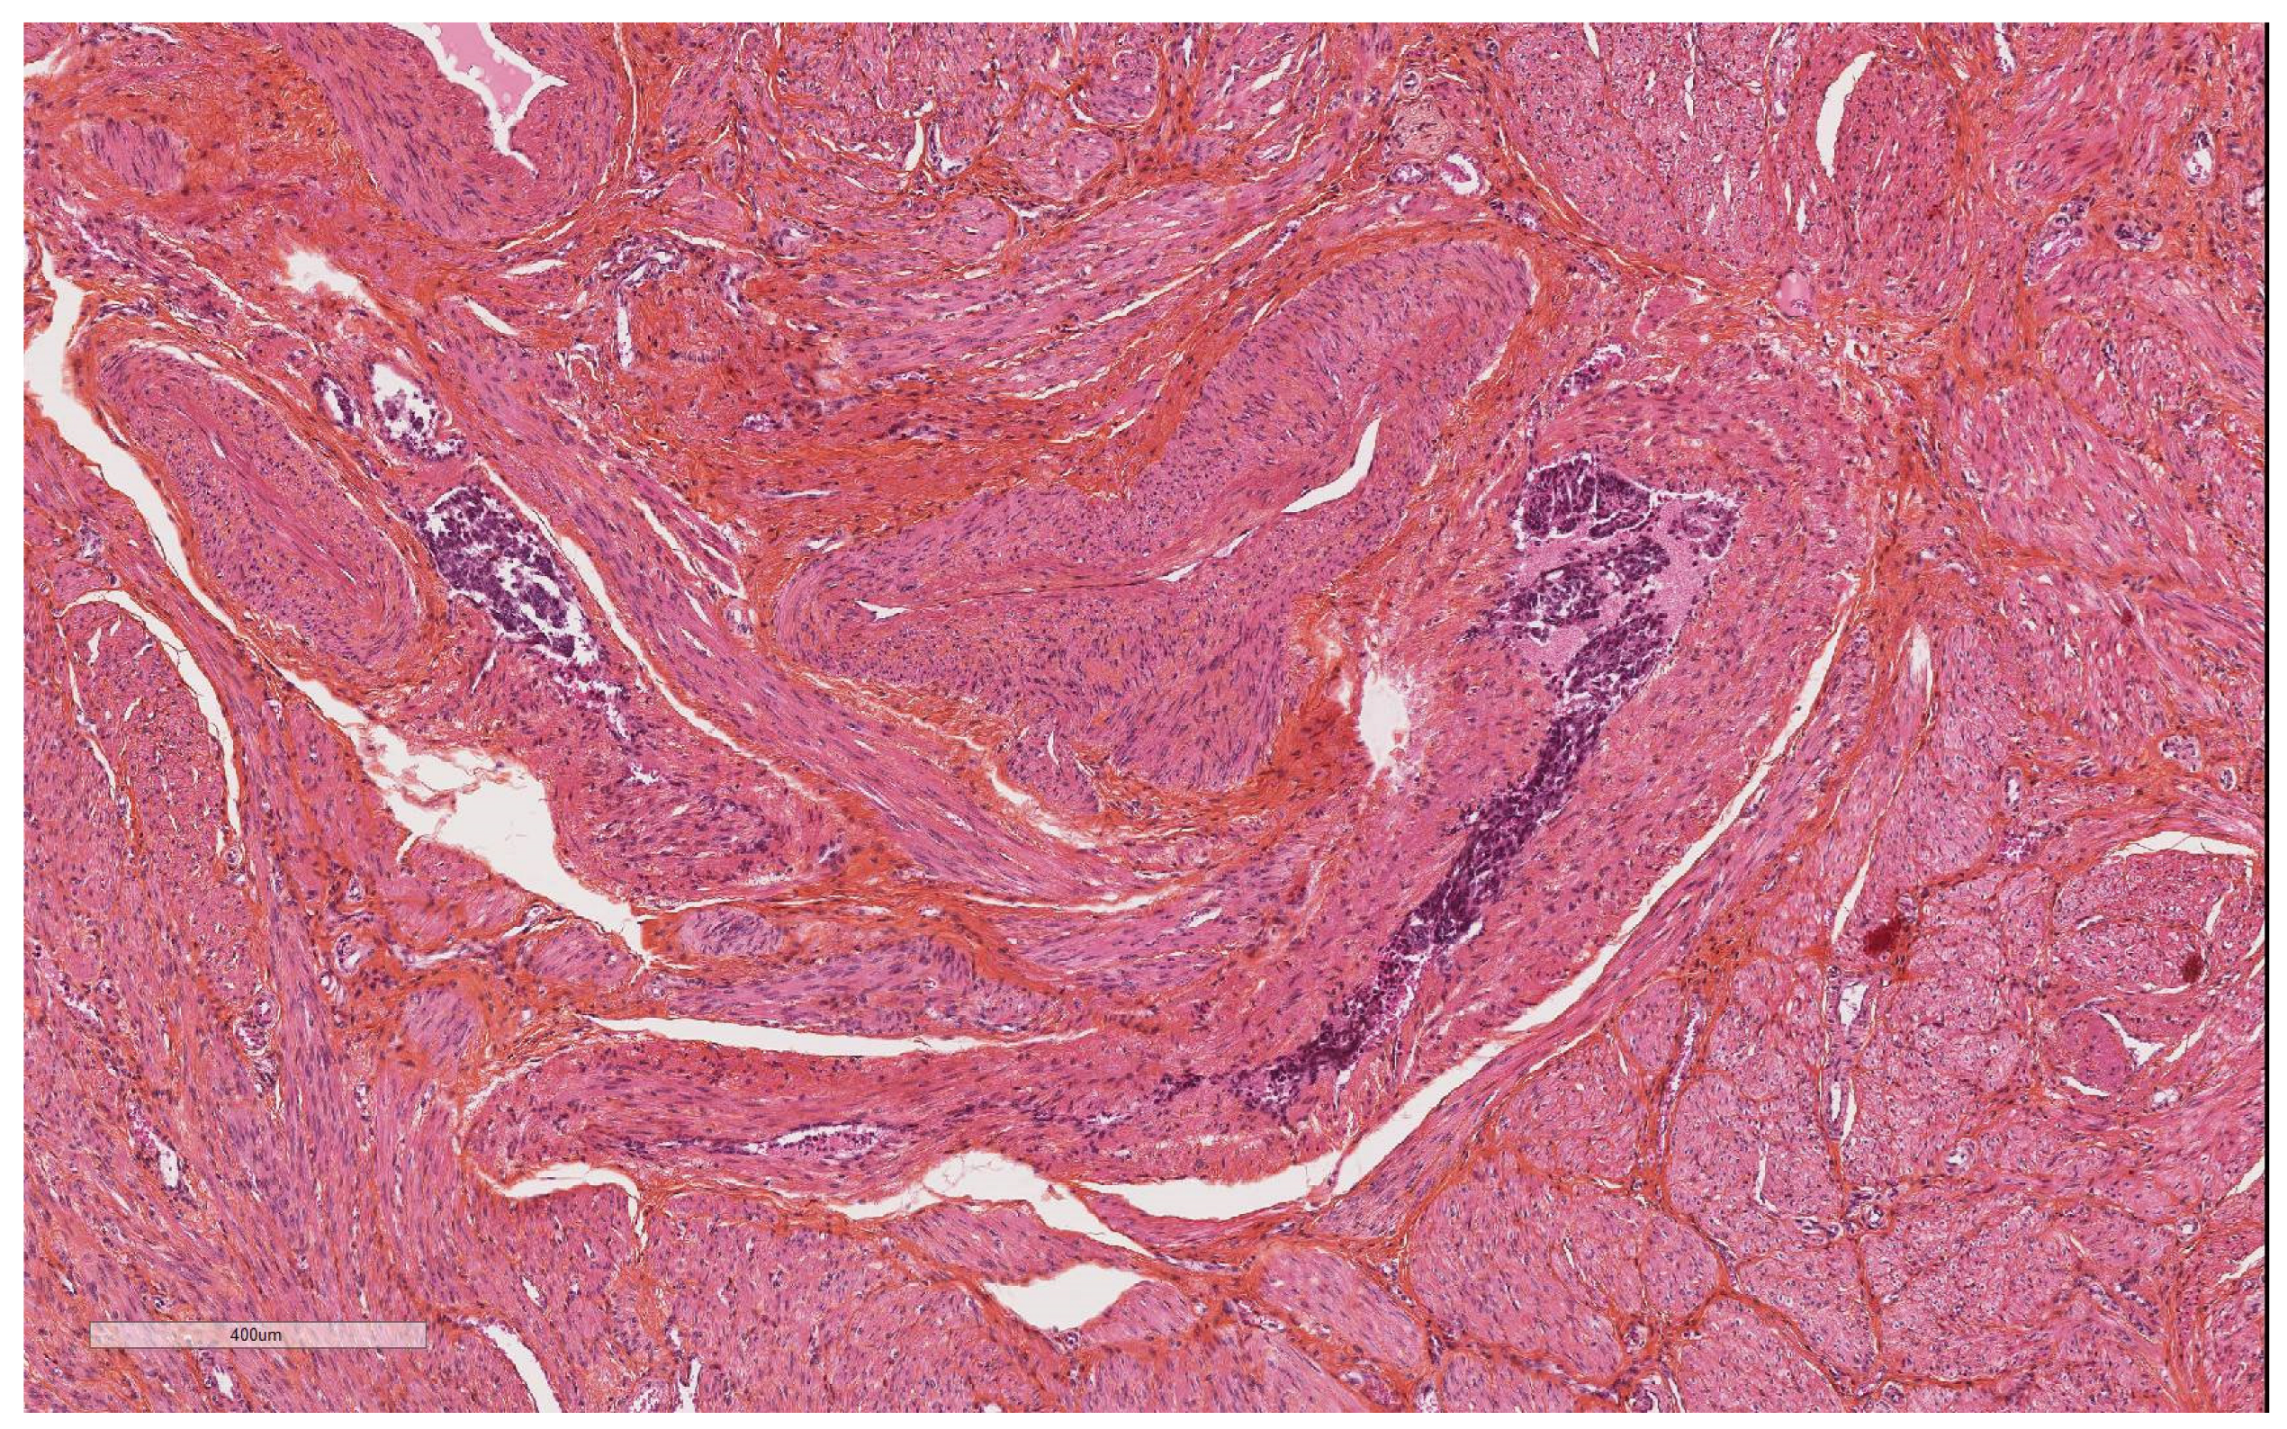

Artefacts in Hysterectomies with a Special Focus on Vascular Pseudoinvasion

| Vascular pseudoinvasion | |

| Present | 14 (23.7) |

| Absent | 46 (76.6) |